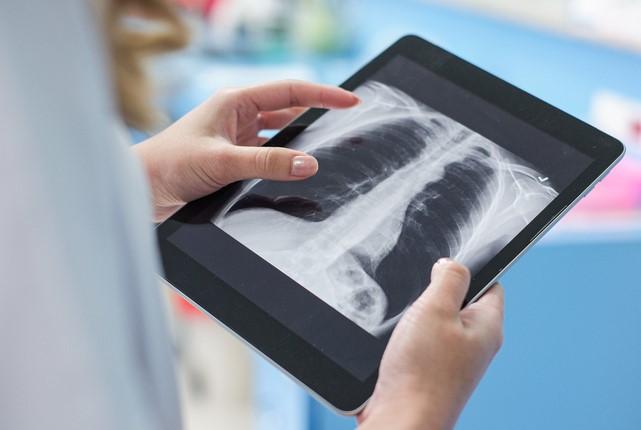

AI fails to reliably detect pediatric pneumonia on X-ray

New research underscores risks of using publicly available large-language AI models in clinical settings.